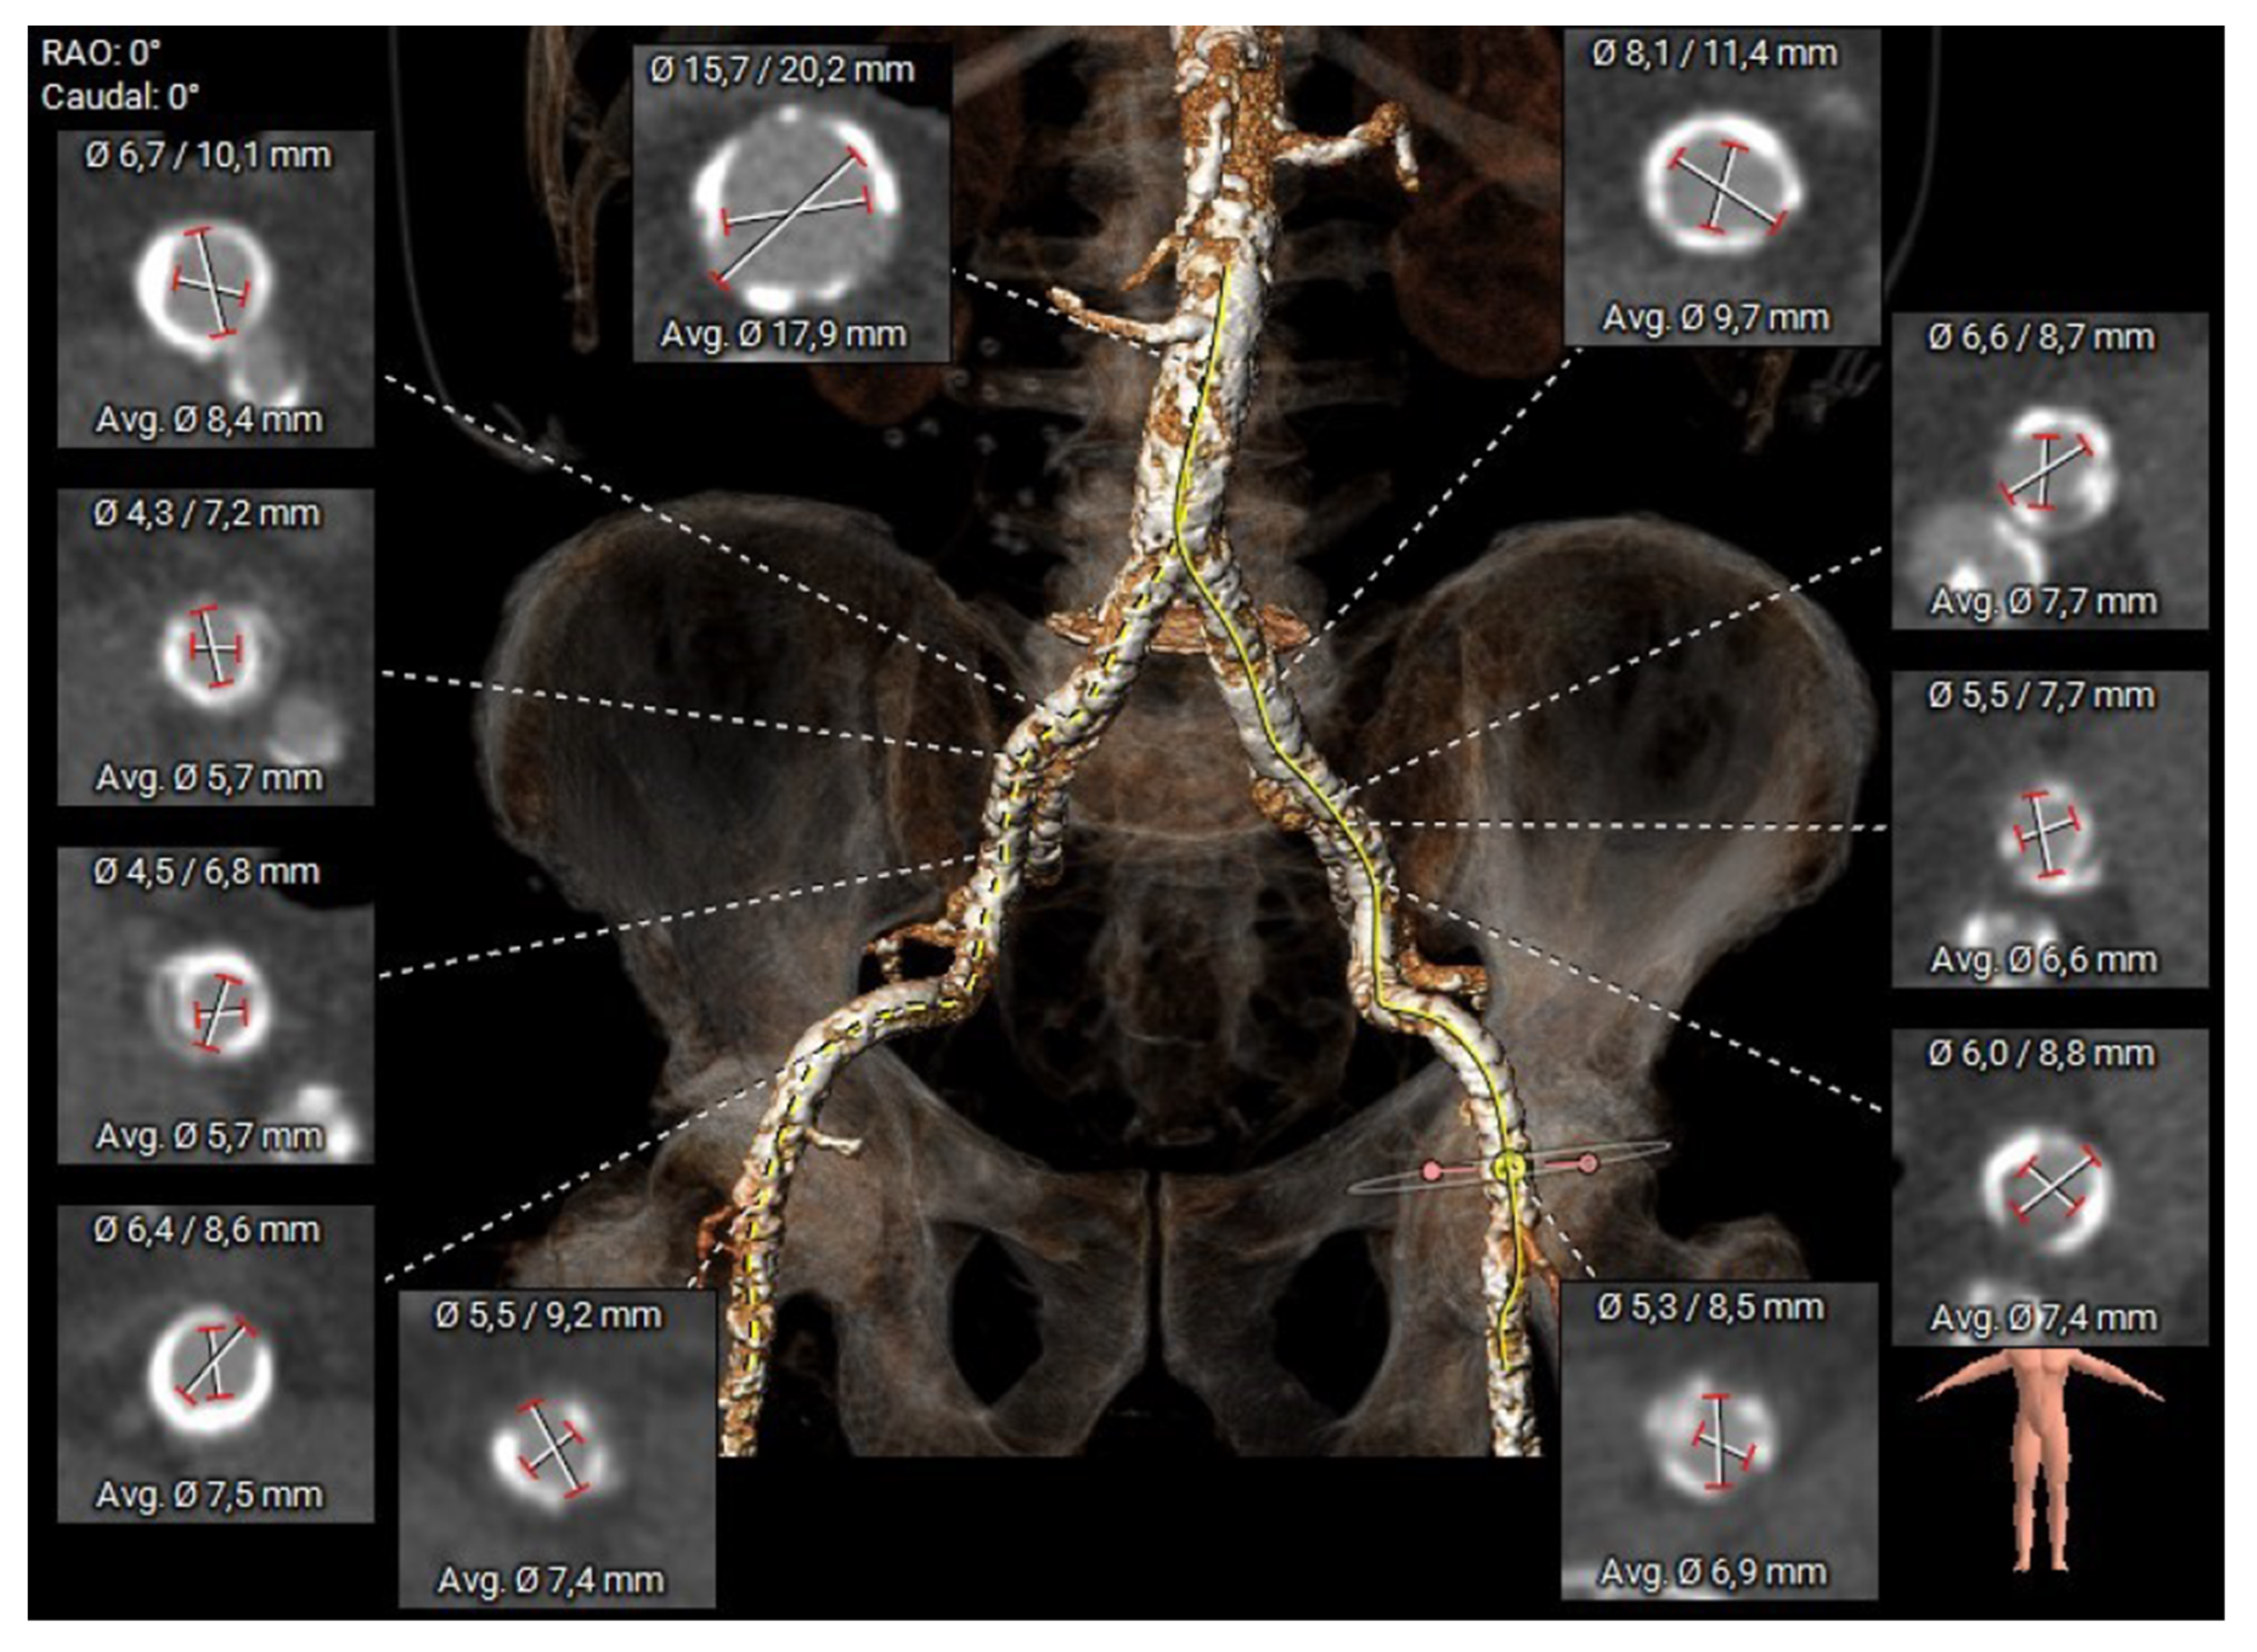

2.2. Preoperative Planning and Operative Technique

2.1. Patient Selection